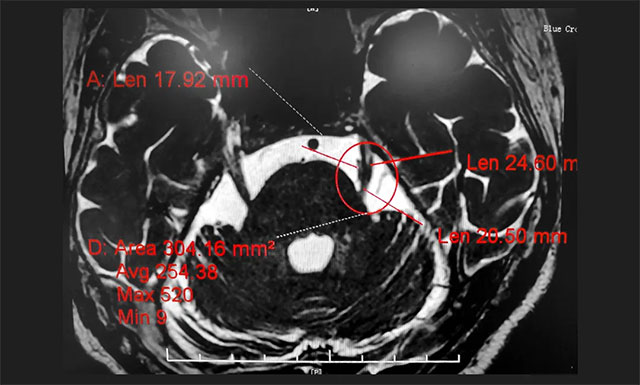

行三叉神經(jīng)磁共振斷層血管成像(MRTA)檢查后,提示患者左側(cè)三叉神經(jīng)與周圍小血管關(guān)系密切。

▲ MRTA檢查提示患者左側(cè)三叉神經(jīng)與周圍小血管關(guān)系密切